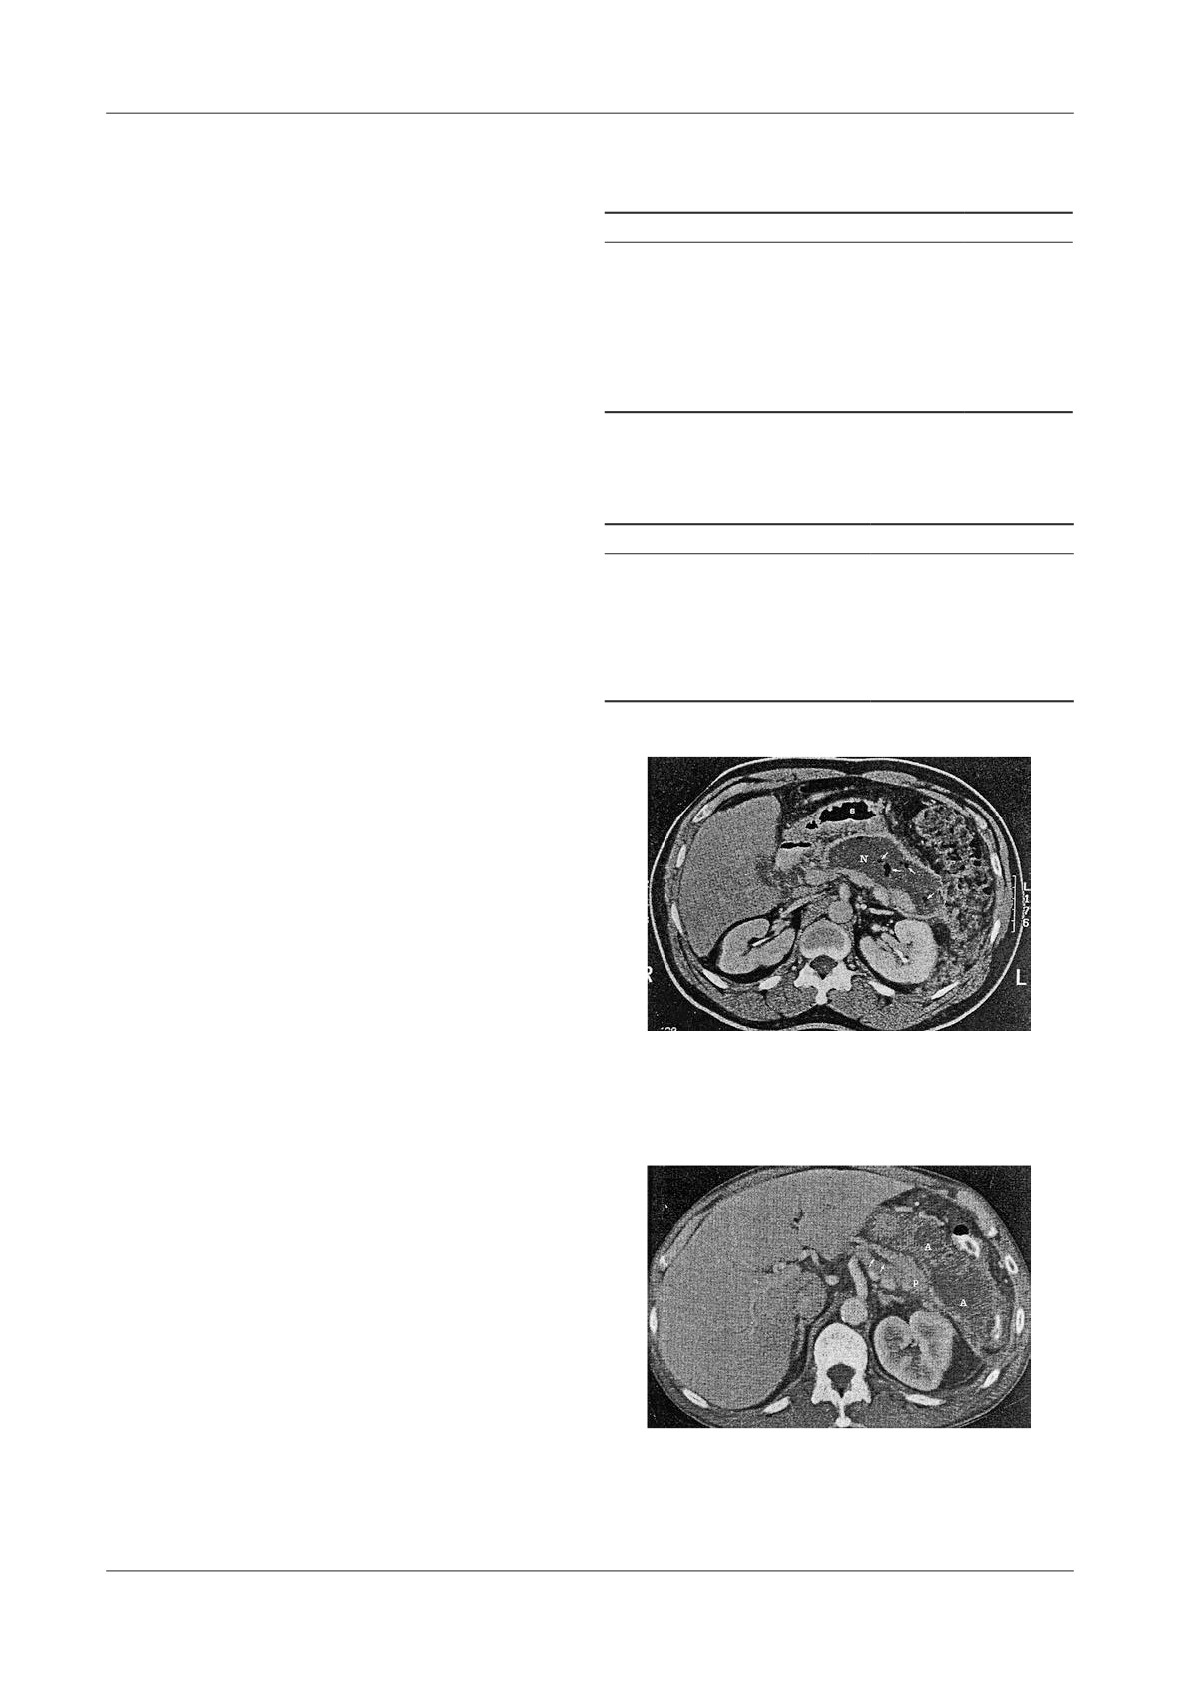

Figure 2. Infected pancreatic necrosis, more of 50% of the

onset (Fig. 2).

CT image is necrosis, with encapsulated liquefaction

According to our experience the detection of gas in

and air bubbles

the necrotic tissue was present in 12% of cases (Figure

2). Such CT  ndings are indicative of infected necrosis.

Figure 3. Pancreatic abscess. 5 weeks following acute

65%.

pancreatitis, heterogeneous  uid collection anterior to the

Cysts >6cm in diameter required surgical treatment

body and tail of the pancreas. Pancreatic ducts are distended

in more than 60%, <6cm in diameter (40%), and acute

Figure 9. Infarcted right colon in A.P. A-CT image shows pseudocyst with pancreatic necrosis

6 weeks following AP, B-One month later CT showed late pneumocystosis

In our study, the detection of gas bubbles in the

of these potentially lethal early complication is complex

necrotic tissue was observed in 12% of cases, and that

(intrapancreatic   activation   of   digestive   enzymes,

was indicative of infection, Figure 2.

In 3% of cases the pancreatic abscess is present in

15%  up  to  55%  of  patients  su ering  from  acute

the evolution of severe pancreatitis, usually 3 to 4 weeks

pancreatitis

[19,20,21].  Profound  respiratory  failure

after  the  onset  of  AP  when  peripancreatic   uid

with ARDS- syndrome occurs in up to 20% in acute

collections are present

[43,44]. A pancreatic abscess

pancreatitis [21].

should be suspected using CT when  uid collections of

Renal complications, with oliguria, can progress to

di erent sizes are depicted in septic patients with a

acute renal failure, which carries a mortality of 80%

recent (3-4 weeks) history of pancreatitis as demonstrated

[22,23].

in our study, and con rmed also in Banks’ study [45].